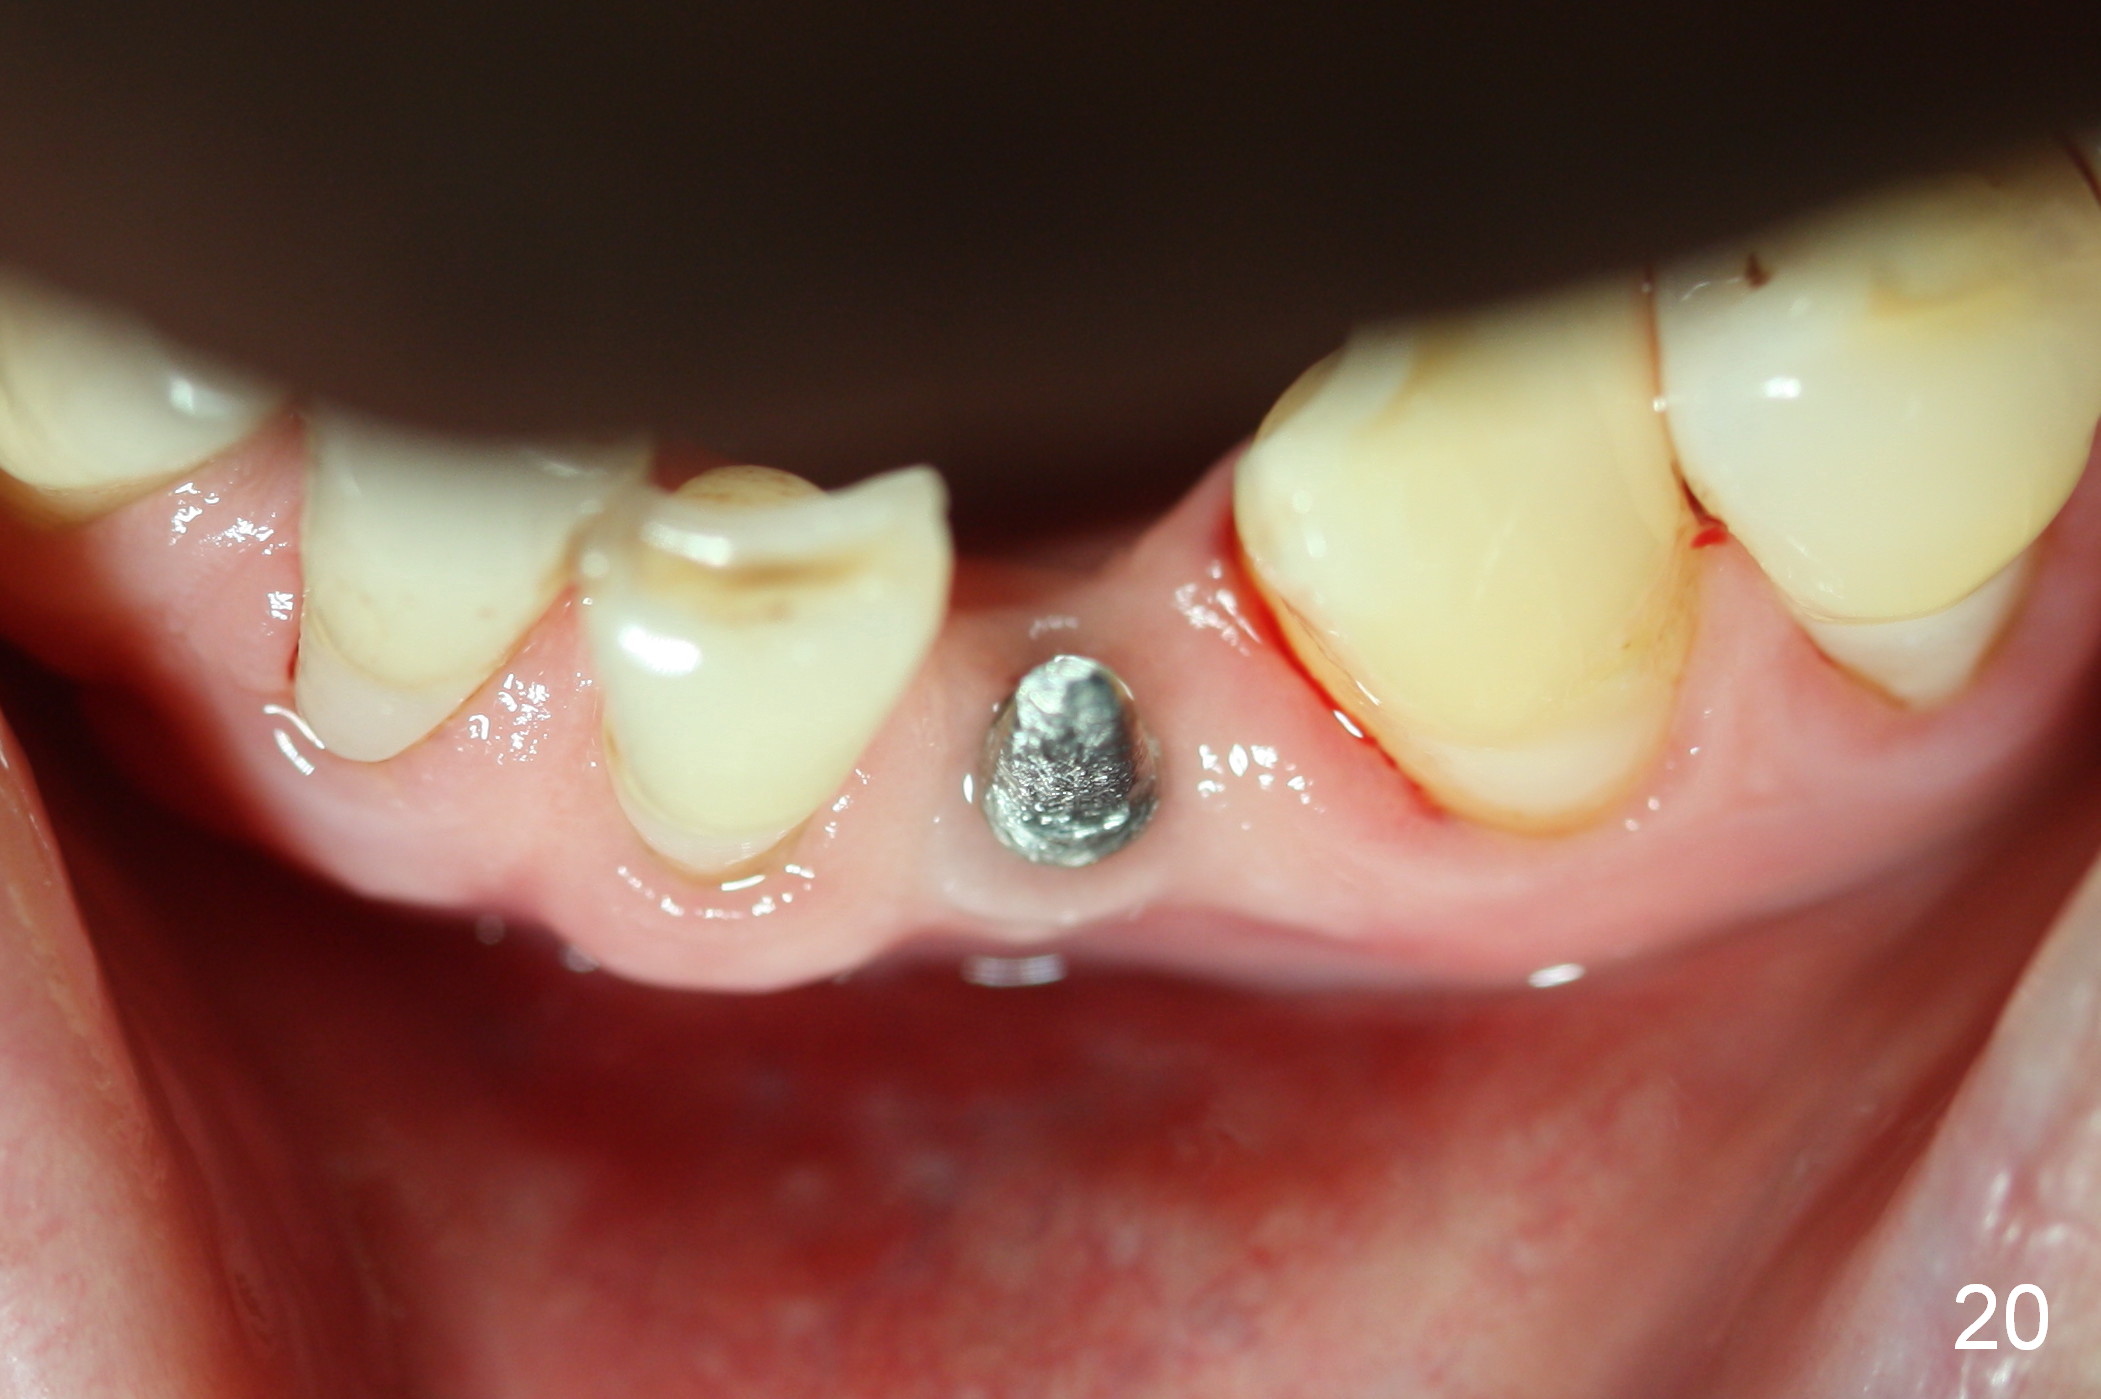

Five months postop, the peri-implant space reduces (Fig.18). A keratinized band forms buccal to the implant (Fig.19 *). The provisional dislodges probably due to the buccal placement (Fig.20).